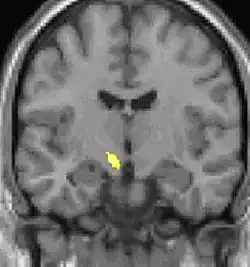

Positron emission tomography (PET) scans indicate the brain areas which are activated during attack only, compared to pain free periods. These pictures show brain areas that are active during pain in yellow/orange color (called "pain matrix"). The area in the center (in all three views) is activated only during cluster headaches. The bottom row voxel-based morphometry shows structural brain differences between individuals with and without CH; only a portion of the hypothalamus is different.[36]